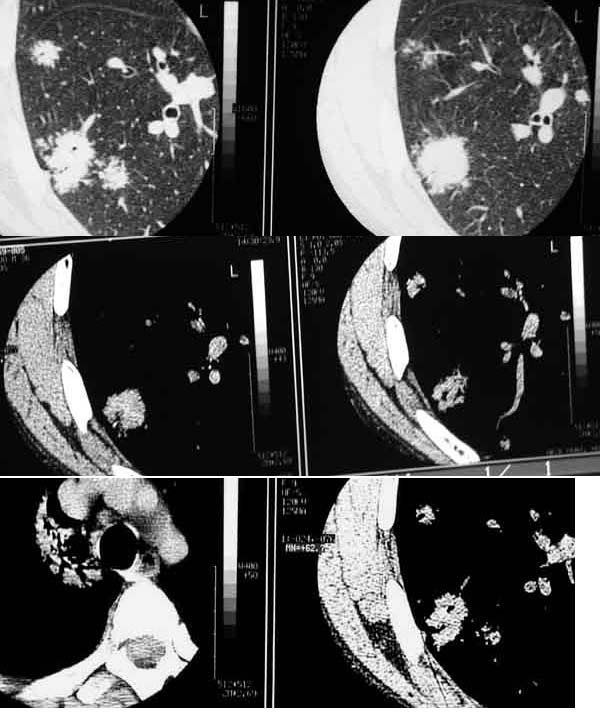

ct 及x线胸片检查示:两肺野可见多发散在结节状密度增高影,直径015~110 cm大小,边界模糊,密度不均,ct 值21.04~33.85 hu。支气管镜检查未见异常,结核菌素试验及痰找结核杆菌3 次均为阴性。。入我院后行胸腔镜下左肺活检术,术中见左肺内多个结节病灶,质地硬,胸膜表面光滑,切取一结节送病理检查。病理检查镜下见病灶区肺泡上皮明显增生,呈腺样结构及乳头状,纤维组织增生形成纤维小结节,呈机化性肺炎改变。病理诊断:肺炎性假瘤伴肉质变,肺泡上皮乳头状增生型。确诊后予地塞米松治疗,复查x线胸片示两肺病灶明显吸收好转